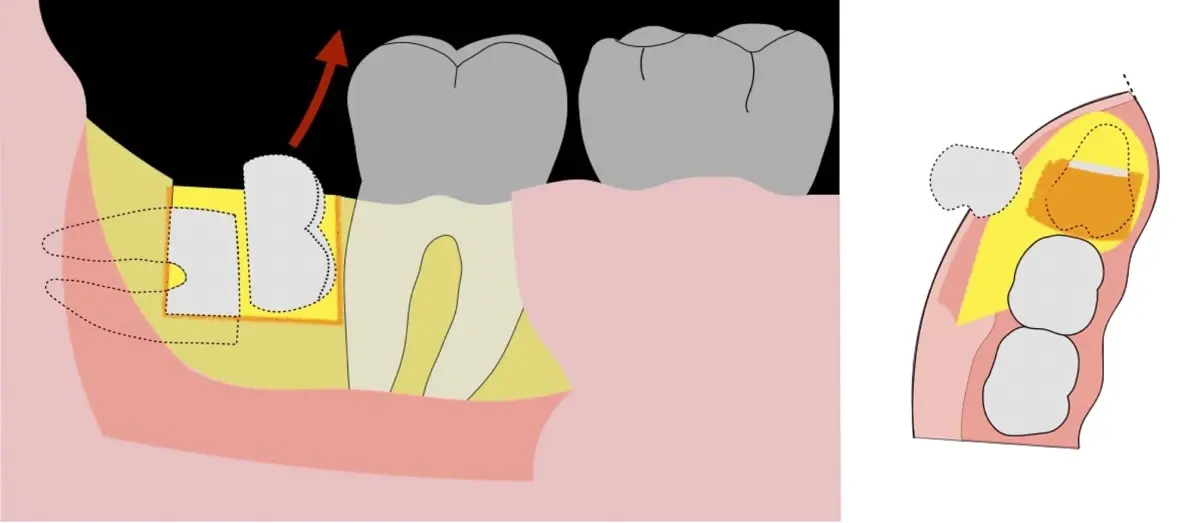

Figura 5. Fractura y eliminación oclusal del fragmento óseo de la porción coronal oclusal.

Figura 6. Demarcación y fractura de la zona de osteotomía a nivel vestibular con inserto aserrado recto y/o angulado.

Figura 7. Eliminación del fragmento vestibular.